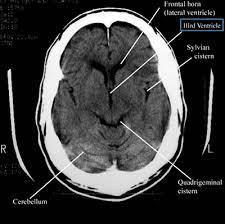

A visit to the physician led to a recommendation for a head CT scan, a diagnostic tool that can peer into the complexities of the human brain. For Rajesh, this suggestion was met with a mix of relief and apprehension. Relief, because it offered a tangible path to understanding his symptoms; apprehension, because the unknown loomed large.

The head CT scan, a non-invasive procedure, promised to reveal the unseen and provide answers that no conversation could. It was recommended for its precision in diagnosing conditions such as tumors, brain injuries, and other neurological disorders. For Rajesh, it was a step into the unknown, but a necessary one.